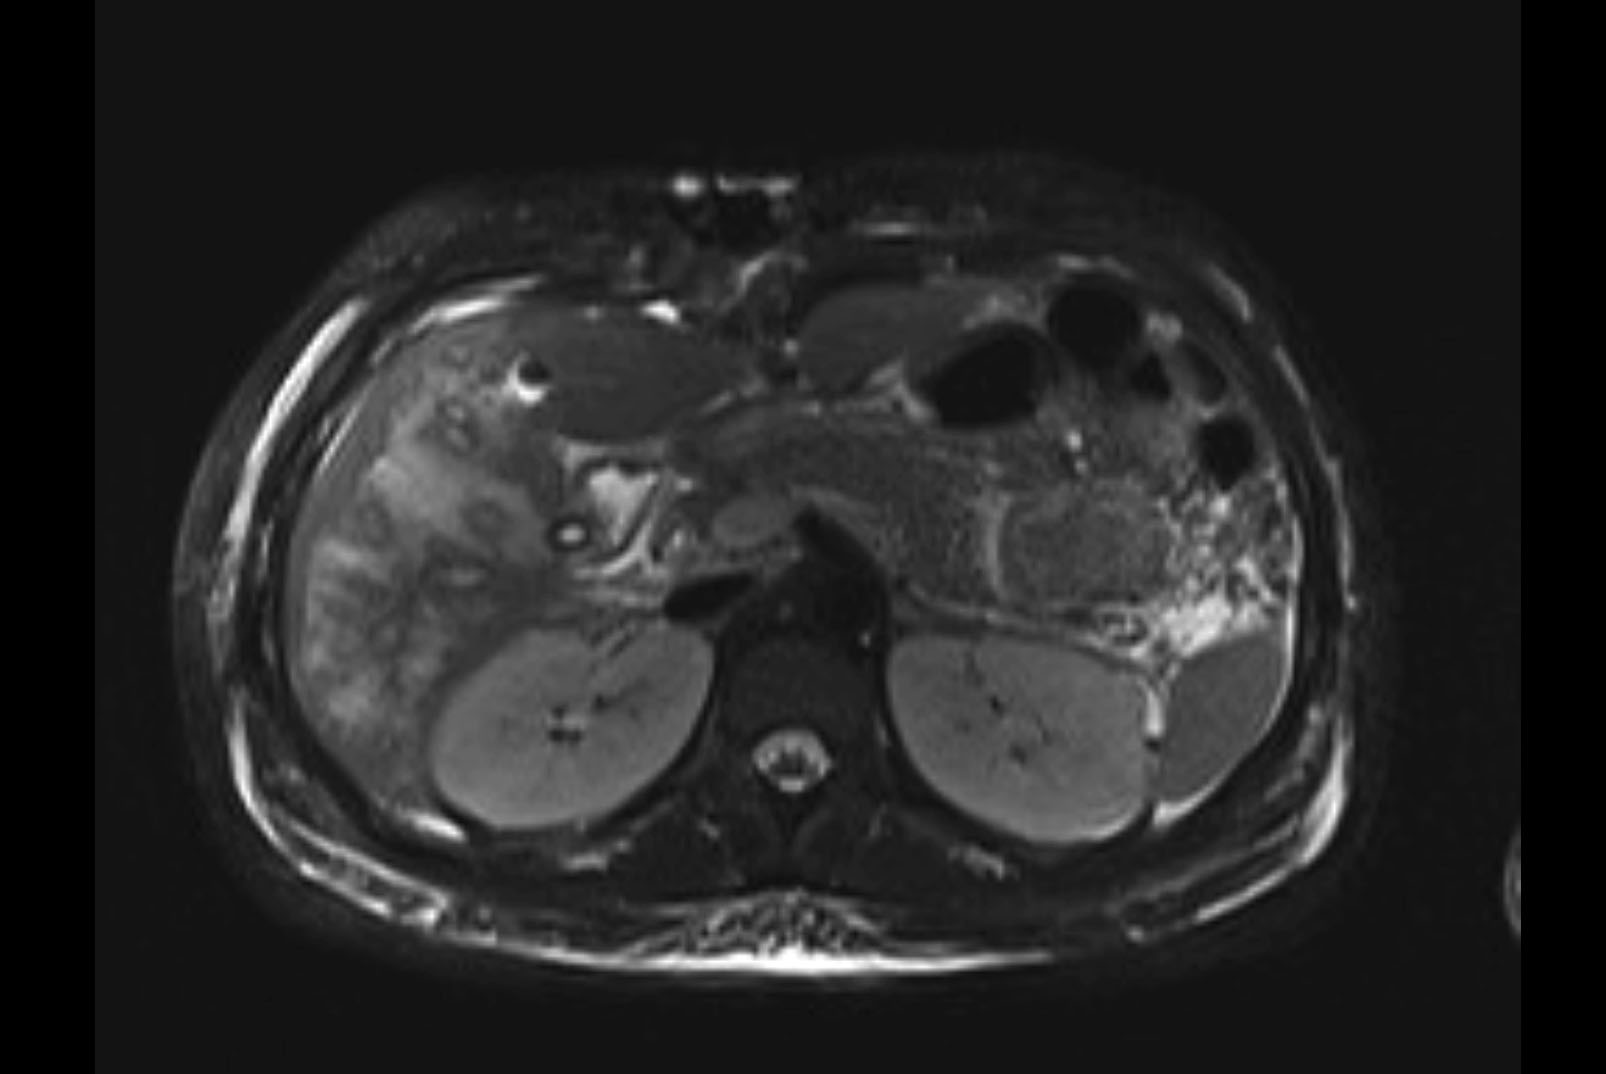

Imaging Analysis

Look through the patient's CT scan to identify any areas of concern for the necessary procedure.

MRI T1

MRI T2

Based on initial findings, which issue(s) would you be most concerned about?